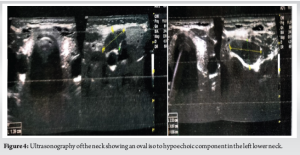

Radiological findings

Radiographs of the thigh revealed a right-sided pathological fracture of the distal femur along with generalized demineralization, bony cysts, osteolysis, and brown tumor (Fig. 1). X-rays of the forearm and hand showed lytic expansile lesions of the 2nd, 3rd, and 4th middle and distal phalanges (Fig. 2). X-ray of the skull revealed multiple lytic lesions with a “salt and pepper” appearance (Fig. 3). Ultrasonography (USG) of the right knee showed an ill-defined hypoechoic heterogeneous lesion on the medial aspect of the lower end of the femur with increased vascularity. USG of the neck revealed an oval iso to a hypoechoic component in the left lower neck, measuring 23.3 × 9.7 × 20.3 mm (Fig. 4). Magnetic resonance imaging of the right knee showed a large mass (7 × 2.9 × 5.8 cm) involving the distal end of the femur, including the diaphysis, metaphysis, and epiphysis, with a pathological fracture, soft tissue edema, and mild fluid collection in the distal thigh (Fig. 5). USG guided fine needle aspiration cytology of the lesion over the right distal femur was done which was suggestive of-giant cell-containing lesion. High-resolution computed tomography of the thorax revealed an expansile osteolytic lesion in the manubrium sterni, right head of the humerus, body of the right scapula, and multiple rib fractures. In addition, hypersensitivity pneumonitis, cardiomegaly, and mild hepato-splenomegaly were noted. USG of the abdomen showed mildly increased periportal echogenicity, a simple cyst (10 × 12 mm) at the midpole of the right kidney, increased bilateral renal echogenicity, and a few mesenteric lymph nodes (average size 10 × 5 mm) with maintained pancreatic hilar architecture. Although a sestamibi scan was highly recommended to confirm the diagnosis of PHPT, it was not performed due to the patient’s low economic status. The provisional diagnosis was a pathological fracture of the right distal femur with secondary osteoporosis at multiple levels caused by PHPT due to a suspected parathyroid adenoma.